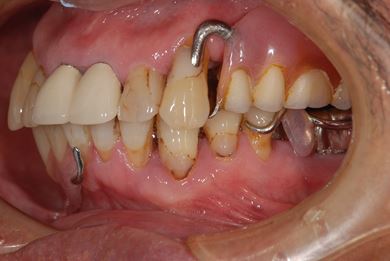

骨再生スピードインプラント治療+遊離歯肉移植

| 性別/年齢 | 男性 / 66歳 | ||||||||||||||||||||||||||||||||

| 主訴 | 入れ歯の部分をインプラントにしたい。 | ||||||||||||||||||||||||||||||||

| 治療方針 | サイナスリフトにより上顎洞を拳上し、インプラント治療を可能にする。 | ||||||||||||||||||||||||||||||||

| 治療内容 | インプラント8本(サイナスリフト、抜歯即日スピードインプラント)、ハイブリッドセラミッククラウン9本、遊離歯肉移植 | ||||||||||||||||||||||||||||||||